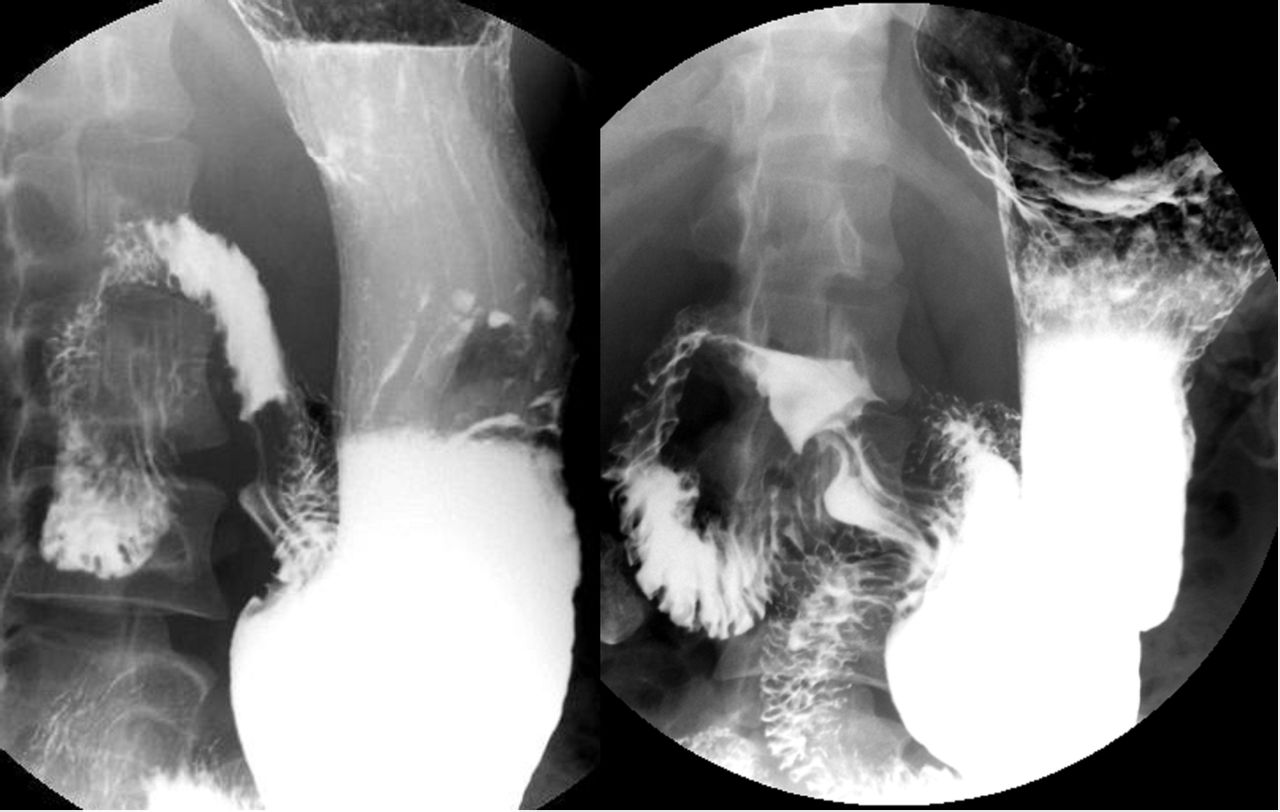

钡餐双重造影